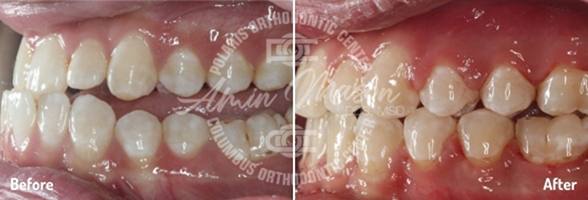

Case 1

Following teenage female patient visited our office with the chief complaint of “crooked teeth.” The patient expressed not being happy with her smile and was not eager to smile. They presented with mild class 2 occlusion, crowding of arches, and crossbite of maxillary lateral incisor teeth. The patient did not wish to have braces and requested clear aligners. She was treated with Invisalign clear aligners and elastics. Total treatment time was 26 months. Patient achieved excellent results.